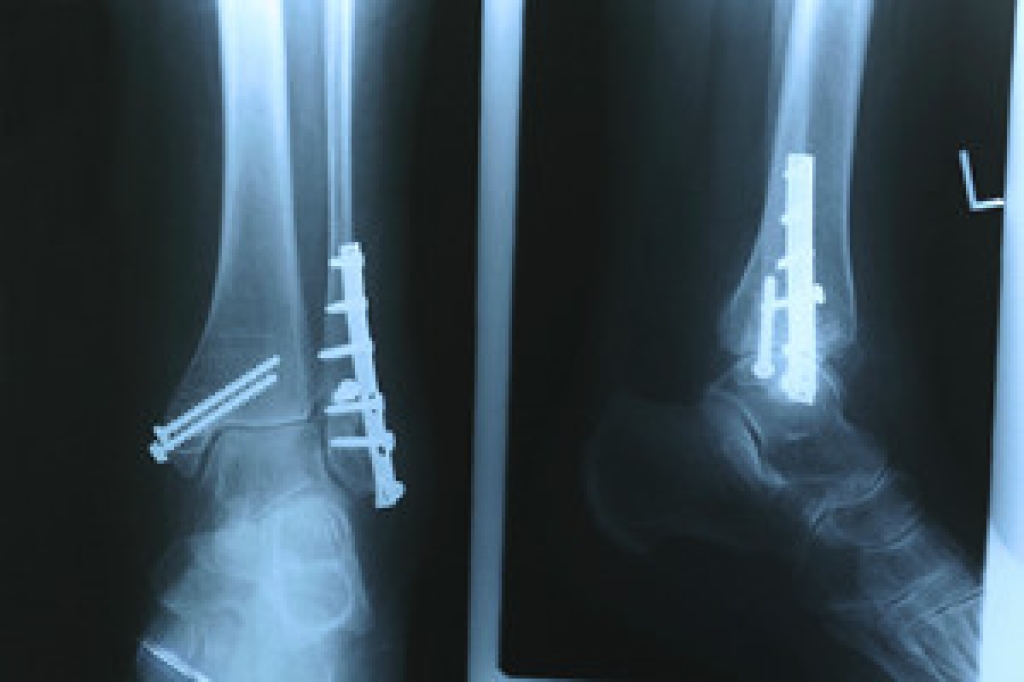

There are a variety of treatment options available for plantar fasciitis along with the pain that accompanies it. Additionally, physical therapy is a very important component in the treatment process. It is important that you meet with your podiatrist to determine which treatment option is best for you.